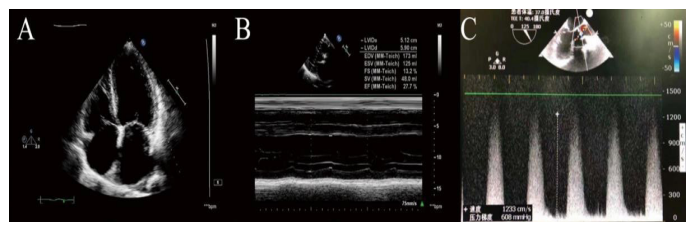

The patient was then transferred to CCU and carefully weaned off catecholamines. He was extubated two days later when BNP decreasing to 4667 Wm. The IABP was removed on the fourth postoperative day. Simultaneously. renal and re- spiratory function was gradually improved. lhe patient was discharged from hospital 1 1 days after surgery without anycom- plications. In the six-month follow-up, the patient's cardiac func- tion was improving fronNYHA class IV to II. Additionally, the ITE showed the mean transvalvular gradient and AVA were 16 mmHg and 1.4 cm2 respectively, and LVEF increased to 48% without any

inotropic agents support (Figure 3).